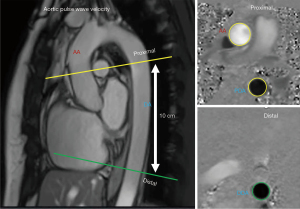

MRI was performed using a 3T scanner (Siemens Healthineers, Erlangen, Germany), with ECG-gating and a phased-array receiver coil (C.P. Body Array Flex; Siemens Healthineers). Details of the MRI protocol can be found in the Appendix 1. To assess MRI-aPWV, two separate through-plane phase-contrast images were acquired: (I) at the level of the ascending aorta, and (II) ~10 cm distal, along the descending aorta. The distance between the ascending and descending images was manually determined from a sagittal image of the aortic arch. All image analyses were performed using commercially available software (CVI42 version 5.6.8; Circle Cardiovascular Imaging Inc., Calgary, AB, Canada). The distance between ascending and the distal portion of descending aorta was measured between the precise locations where the through-plane phase-contrast images were collected using an oblique sagittal image through the thoracic aorta. The aortic transit time was calculated as the average time difference between the systolic upslope of the ascending and descending aortic flow curves. aPWV was calculated as the distance between the ascending and descending aorta, divided by the transit time between the two aortic locations (Figure 1).